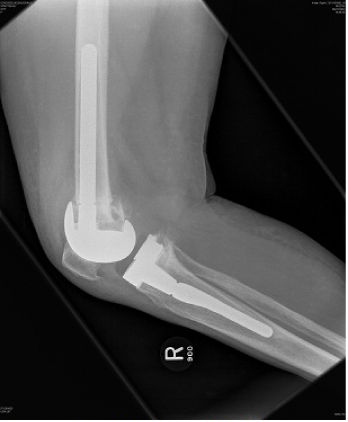

Post operatively, full ROM and full weight bearing was permitted from post-operative day two. By six week follow up the patient was fully weight bearing without any aids; radiographs demonstrated bony union at the osteotomy site with good alignment (Figure 4–6). At one year review, the patient was pain free, with a ROM of 0° to 110° without a quadriceps lag, and with clinically acceptable alignment (Figure 7). Pre and postoperative knee scores are listed in Table 1.

Figure 5 Postoperative AP view of the knee.

Figure 6 Postoperative lateral view of the knee.

In the literature to date there has not previously been a report of a simultaneous peri-articular femoral osteotomy and total knee arthroplasty for a severe arthritic valgus knee of >45°. In this patient, excellent alignment both clinical and radiological was obtained, with the valgus deformity improving from 45° to 7° of valgus. Symptomatically, at 1 year follow up the patient is doing extremely well with good ROM and is pain free, without any complications. We believe that this operative technique in severely valgus knees allows for excellent correction of malalignment, aids soft tissue balance with good patient outcome.